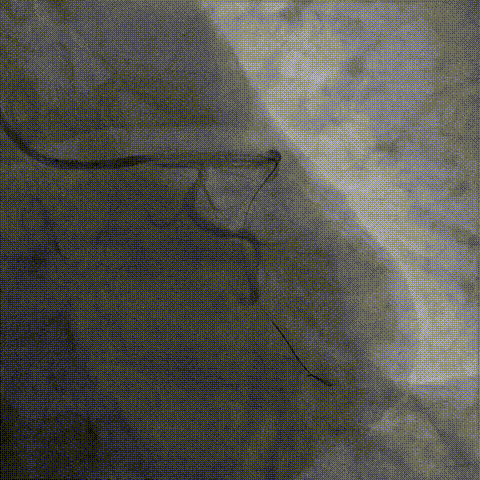

右冠PCI

器械通过困难:

1、正向导丝通过后,微导管无法跟进,尝试1.25、1.5mm球囊均无法通过病变。

2、6F Telescope™导引延长导管支撑下1.25mm球囊通过病变预扩后换用2.0mm球囊完成预扩张。

1、2.0mm球囊预扩张后球囊顺利进入Telescope™导引延长导管锚定导丝,送入Finecross微导管,后交换Pilot200导丝为Runthrough导丝。

2、6F Telescope™导引延长导管可兼容2号2.0mm预扩球囊及Finecross微导管同时进入,具有良好的内腔兼容性。

2.0mm球囊进入Telescope™锚定,通过无阻力

2.0mm球囊锚定导丝后微导管进入Telescope™内腔兼容性强